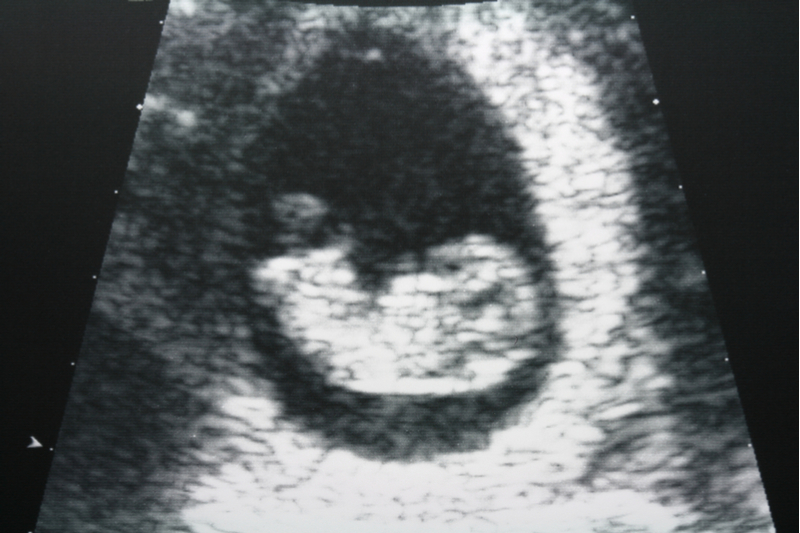

妊娠の初診時には、経腟によるエコー検査も行われます。子宮外妊娠や絨毛性疾患などの妊娠異常がないかを確認するためです。経腟エコーでは、妊娠週数や子宮内膜の状態もわかります。

妊婦健診で経腟エコーから腹部エコーに切り替わるタイミングは、病院によって異なります。しかし、胎児の発育が進む妊娠12週頃になると、胎児の大きさをはかる大腿骨長(FL)や児頭大横径(BPD:頭蓋骨の外側から反対側の頭蓋骨の内側までの距離)の測定が可能になるため、12週~16週頃に腹部エコーによる検査が始まるのが一般的です。